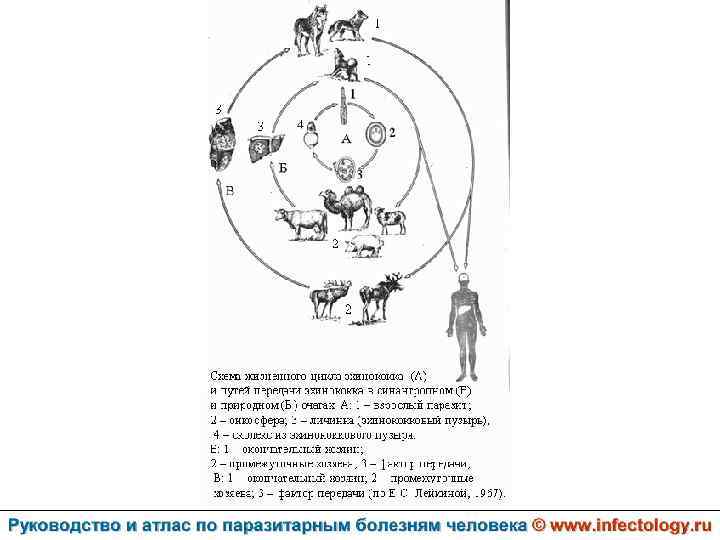

Цистный эхинококкоз (цистный гидатидоз) (шифр по МКБ 10 - B 67. 0 -4) – зоонозный биогельминтоз, характеризующийся хроническим течением, образованием кист и деструктивным поражением печени, легких и других органов.